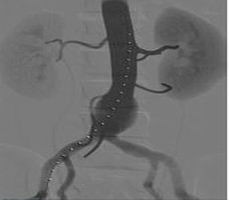

腹主動脈瘤修復(fù)手術(shù)模塊

可練習(xí)主動脈造影、主干精確開傘、對側(cè)腿使用腹膜支架、支架打開、球囊擴張等操作